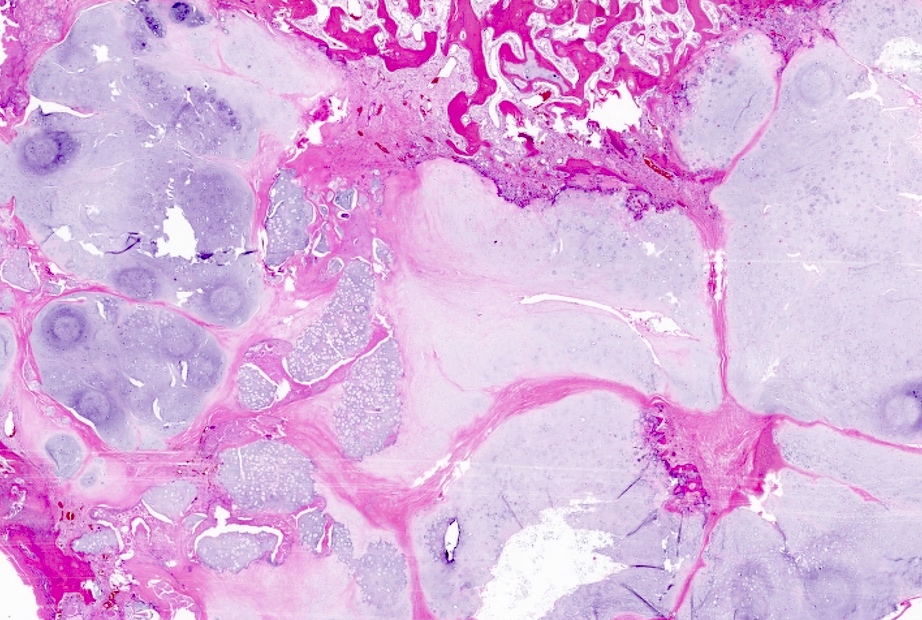

Microscopic (histologic) description

- Lobulated growth pattern (J Dent Res Dent Clin Dent Prospects 2011;5:98)

- Lobules have irregular shapes and sizes and may be separated by fibrous bands containing small vessels (Virchows Arch 2012;460:95)

- Lobules are composed of abundant hyaline cartilage matrix (sometimes with mucoid / myxoid changes) and permeate and entrap lamellar bone trabeculae

- Cellularity is slightly higher than in enchondroma

- Cells show moderate eosinophilic to vacuolated cytoplasm

- Nuclei are small and uniform with condensed chromatin (lymphocyte-like); sometimes they show open chromatin with visible nucleoli (Am J Surg Pathol 2009;33:50)

- Mitoses and significant nuclear pleomorphism are absent

- Binucleation can be observed

- Necrosis can be seen

- In cases arising from pre-existing enchondromas, areas of enchondroma with calcifications can be present

- In cases arising from pre-existing osteochondroma, evidence of this tumor can be seen (Mod Pathol 2012;25:1275)

Microscopic (histologic) images

Practice question #1

A 41 year old woman complained of an enlarging mass at her left proximal humerus. Xrays showed a lucent lesion with indistinct borders and endosteal scalloping. MRI showed an irregular, expansile, avidly enhancing mass. A biopsy of the lesion was performed and is shown above. What is the diagnosis?